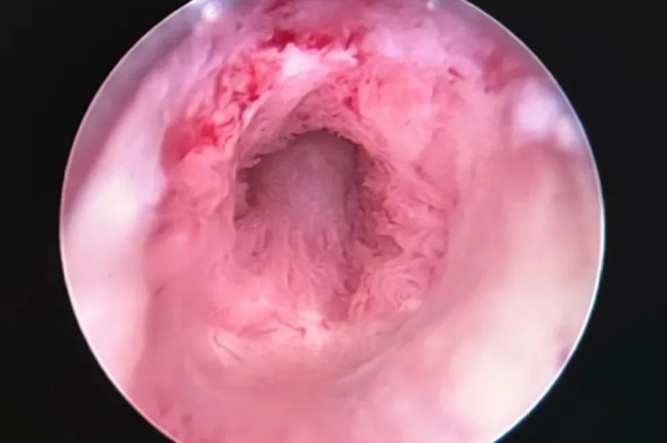

手術(shù)歷時(shí)3小時(shí),過程順利,手術(shù)后3周成功拔除尿管,小便順暢,膀胱鏡檢查評(píng)估后,尿道吻合口愈合良好。